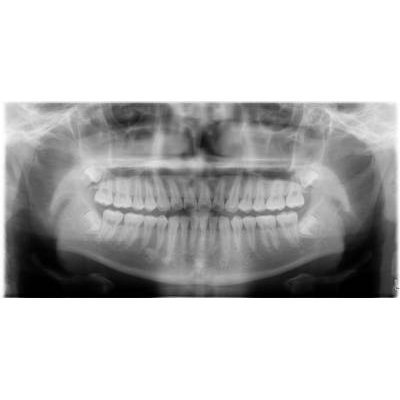

兒童牙科